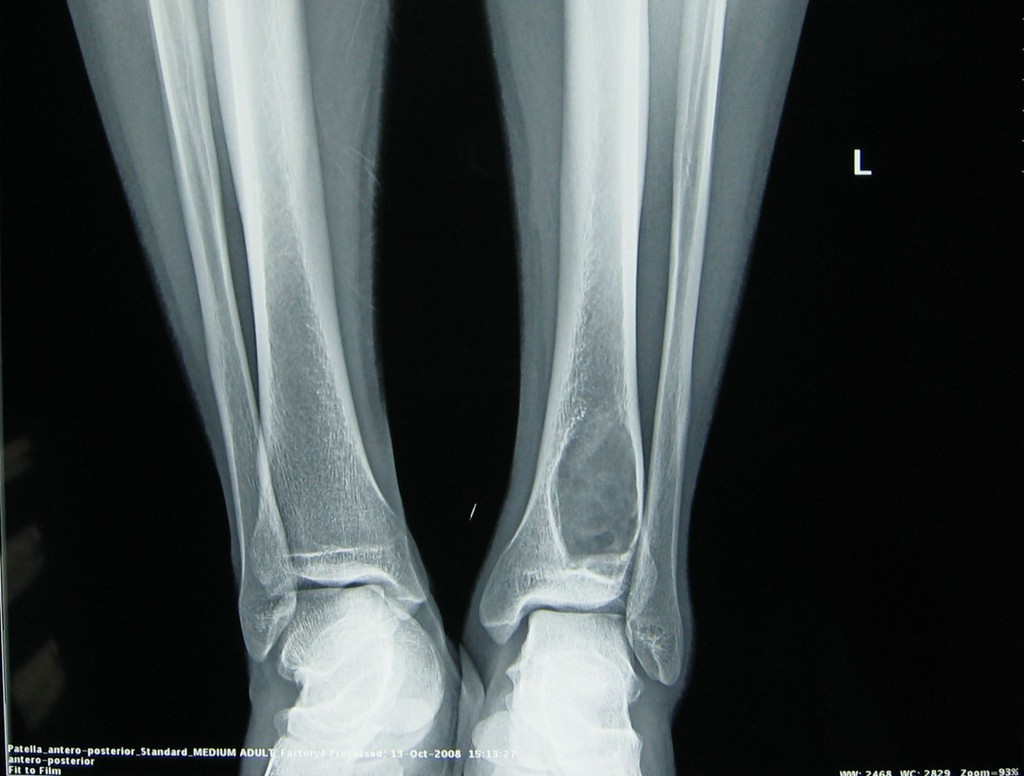

骨样骨瘤 注:胫骨干 前方骨皮质内有 一直径约1cm之 瘤巢,周围

【读片】(病理已公布)胫骨病变平片,ct,mri随你看(有个坑)(有病理结果

左胫骨平台骨巨细胞瘤一例